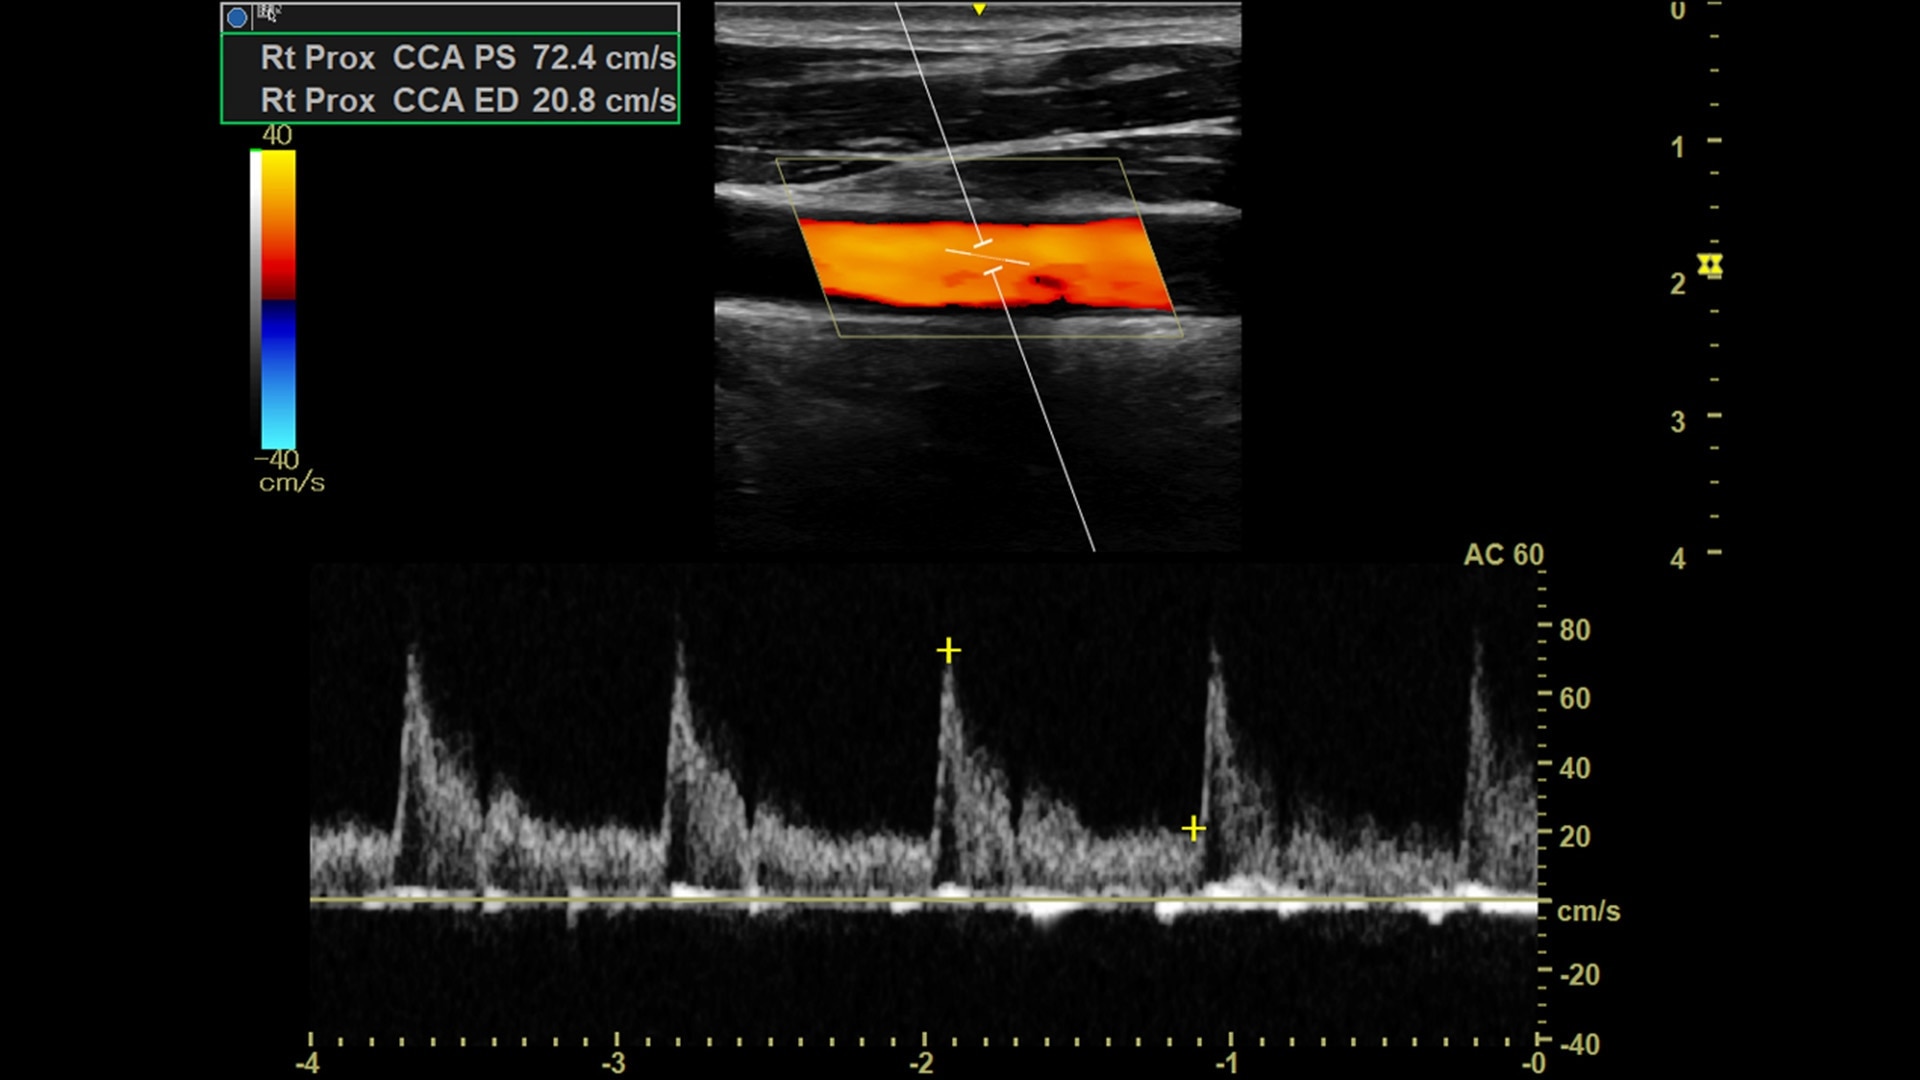

Efficient

Simple-to-use design, workflow and automated tools streamline workflow